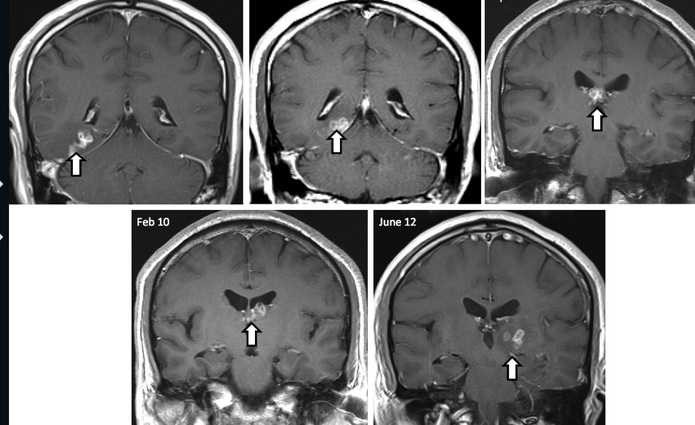

| Loài giun này di chuyển trong não người đàn ông trong theo các mốc thời gian |

"Khi anh ta trở lại, anh ta gặp phải những triệu chứng mới" - Bác sĩ Gkrania-Klotsas nói về bệnh nhân của mình. Có thể lý giải rằng, con giun đã di chuyển sang một vùng khác của não bộ, khiến cho việc vận động các chi của người đàn ông kém dần đi. Hội chứng này gọi là Sparganosis (bị ảnh hưởng từ ký sinh trùng).

Như vậy, bệnh nhân cần chữa trị ngay và tất nhiên là chưa thể có thuốc đặc trị. Các bác sĩ đã quyết định sử dụng phương pháp phẫu thuật trực tiếp để loại bỏ loài ký sinh trùng khỏi não bộ của người đàn ông này.